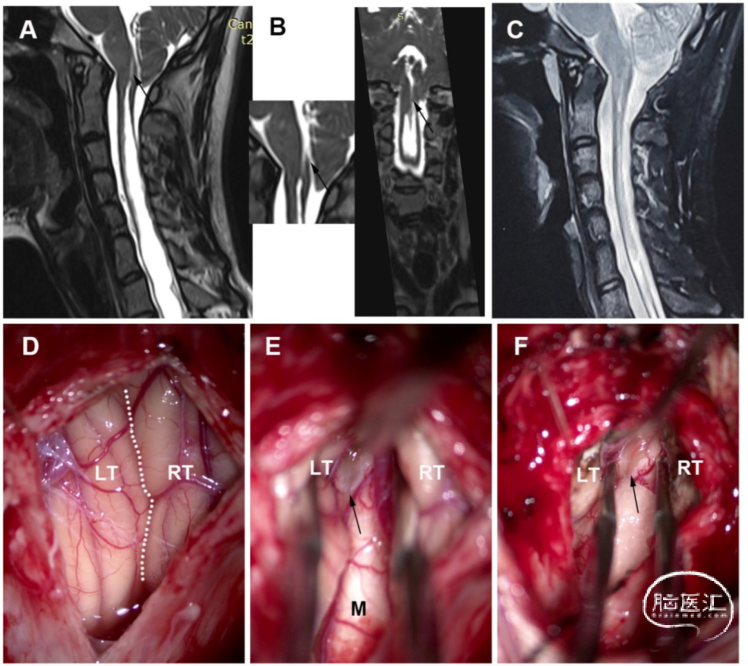

男性,29岁,有10年头痛和颈部疼痛病史。术前MRI显示,SM延伸至C1水平的下缘,不与第四脑室相通。术中见,扁桃体居中,占据枕骨大孔,并覆盖Magendie孔。进行软膜下扁桃体切除术。术后MRI显示,SM的大小明显缩小。术后症状部分缓解(图4)。

图4. 非交通型CM-SM病例。A. 术前MRI-T2矢状位加权成像。SM向上延伸至C1的下缘。B. 高分辨率MRI显示,SM的上端与第四脑室不连通。C. 术后MRI显示SM明显减少。D. 硬膜切开后,显示中间化的扁桃体占据枕骨大孔和覆盖Magendie孔。E. 显露Magendie孔,脑脊液在其中自由流动(星号)。F. 进行软膜下扁桃体切除术,可以看到Magendie孔(星号)。